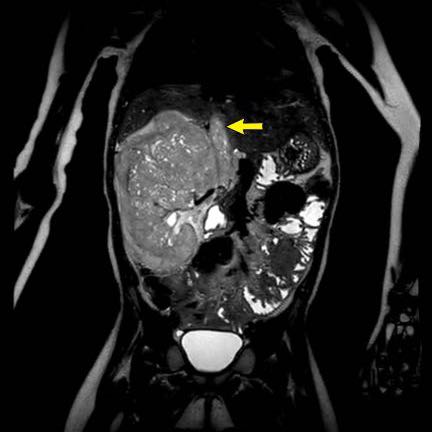

Ca lâm sàng 1

Hình ảnh chuỗi xung T2W mặt phẳng coronal cho thấy một khối u không đồng nhất ở thận trái với các thành phần nang nhỏ.

Khối u ngấm thuốc kém hơn so với phần nhu mô thận bình thường còn lại ở ngoại vi.

Các thành phần đặc của khối u cho thấy hạn chế khuếch tán rõ rệt (mũi tên).

Đây là u Wilms ở bé trai năm tuổi. Hóa trị tiền phẫu được thực hiện theo phác đồ Umbrella của SIOP-RTSG, sau đó tiến hành cắt thận.